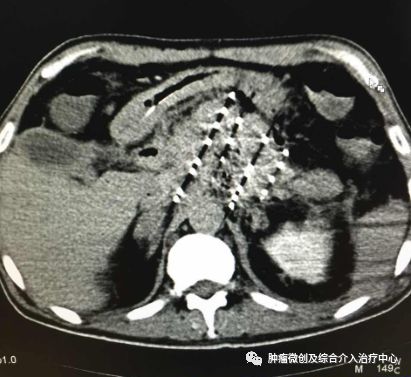

经皮穿刺碘125粒子植入